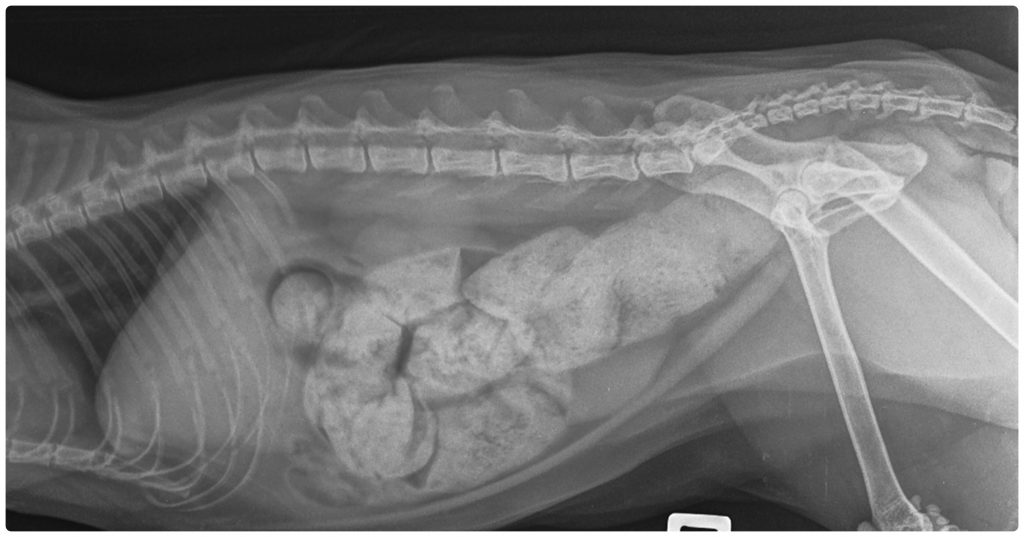

Das Megakolon ist die schwerste Verlaufsform chronischer Verstopfung. Dabei weitet sich der Dickdarm durch wiederholte Überdehnung dauerhaft aus und verliert seine Fähigkeit, den Kot weiterzubefördern. Einige Katzen entwickeln ein Megakolon nach jahrelanger, unbehandelter Verstopfung, andere aufgrund von Beckenverletzungen oder angeborenen Nervendefekten. In einem erheblichen Teil der Fälle lässt sich keine eindeutige Ursache feststellen – man spricht dann von einem idiopathischen Megakolon. Die Diagnose erfolgt in der Regel mittels Röntgenaufnahmen, die eine charakteristische Ausdehnung des Kolons zeigen. Da es sich um eine chronische Erkrankung handelt, ist eine dauerhafte tierärztliche Betreuung notwendig